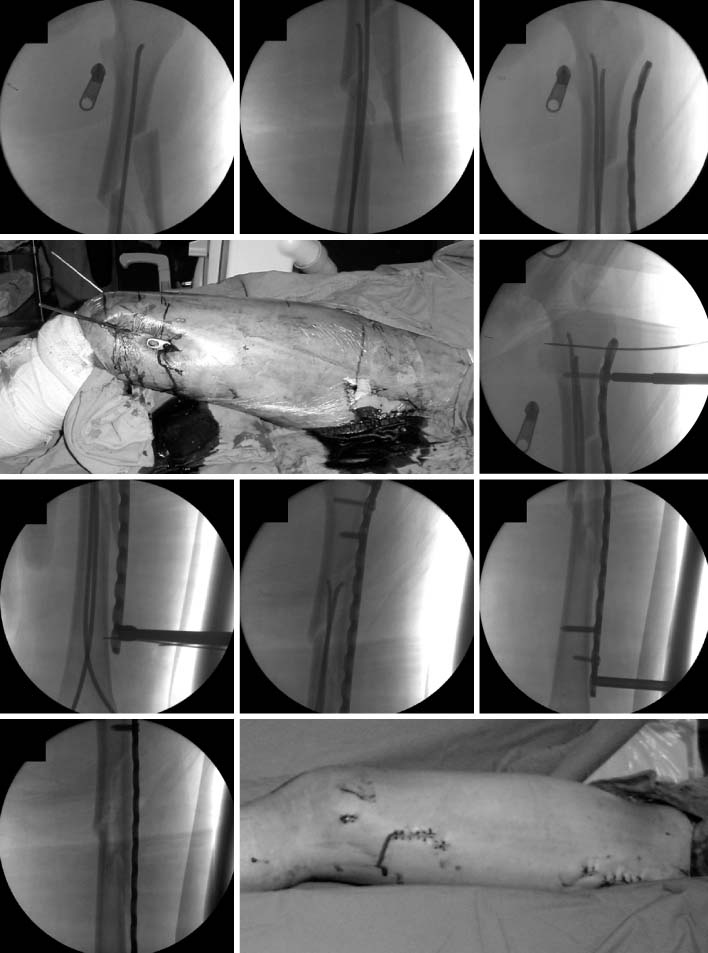

Fig. 5

These are the sequence of operatingprocedure in the suggested patient of Fig. 1. After the temporary reduction of femoral fracture with flexible nails, the plate was introduced through the submuscular tunnel. Then, the locking screws were fixed at the proximal and distal sides of the plate. The fracture site was not open to preserve the biology. The flexible nail makes an easier reduction of fracture, which facilitates the minimally invasive plate osteosynthesis (MIPO) procedure.

Fig. 5 These are the sequence of operatingprocedure in the suggested patient of Fig. 1. After the temporary reduction of femoral fracture with flexible nails, the plate was introduced through the submuscular tunnel. Then, the locking screws were fixed at the proximal and distal sides of the plate. The fracture site was not open to preserve the biology. The flexible nail makes an easier reduction of fracture, which facilitates the minimally invasive plate osteosynthesis (MIPO) procedure.